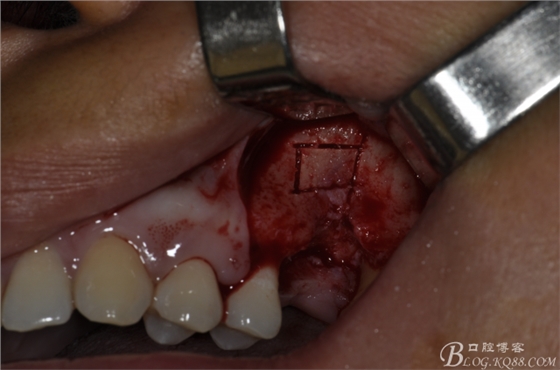

術(shù)中照片。

超聲骨刀切開骨外板 上頜竇外提一例